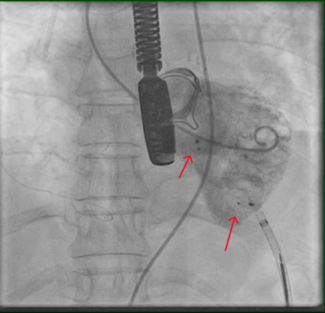

Severe pulmonary hypertension, thickening of tricuspid leaflets with vegetation on the ventricular side, and severe aortic valve thickening and stenosis were noticed on echocardiogram. A flow from aorta to right atrium was also seen. Transesophageal echocardiogram confirmed an aortic annular abscess with aorto-right atrial shunt.

At surgery, a bicuspid aortic valve with heavy calcification and acute infectious debris was noted. There was also an inflamed and indurated area found in the right atrium, which was debrided. The aorta to right atrial fistula was repaired with bicameral pericardial patch. The aortic valve was replaced with a bioprosthesis.

At surgery, a bicuspid aortic valve with heavy calcification and acute infectious debris was noted. There was also an inflamed and indurated area found in the right atrium, which was debrided. The aorta to right atrial fistula was repaired with bicameral pericardial patch. The aortic valve was replaced with a bioprosthesis.